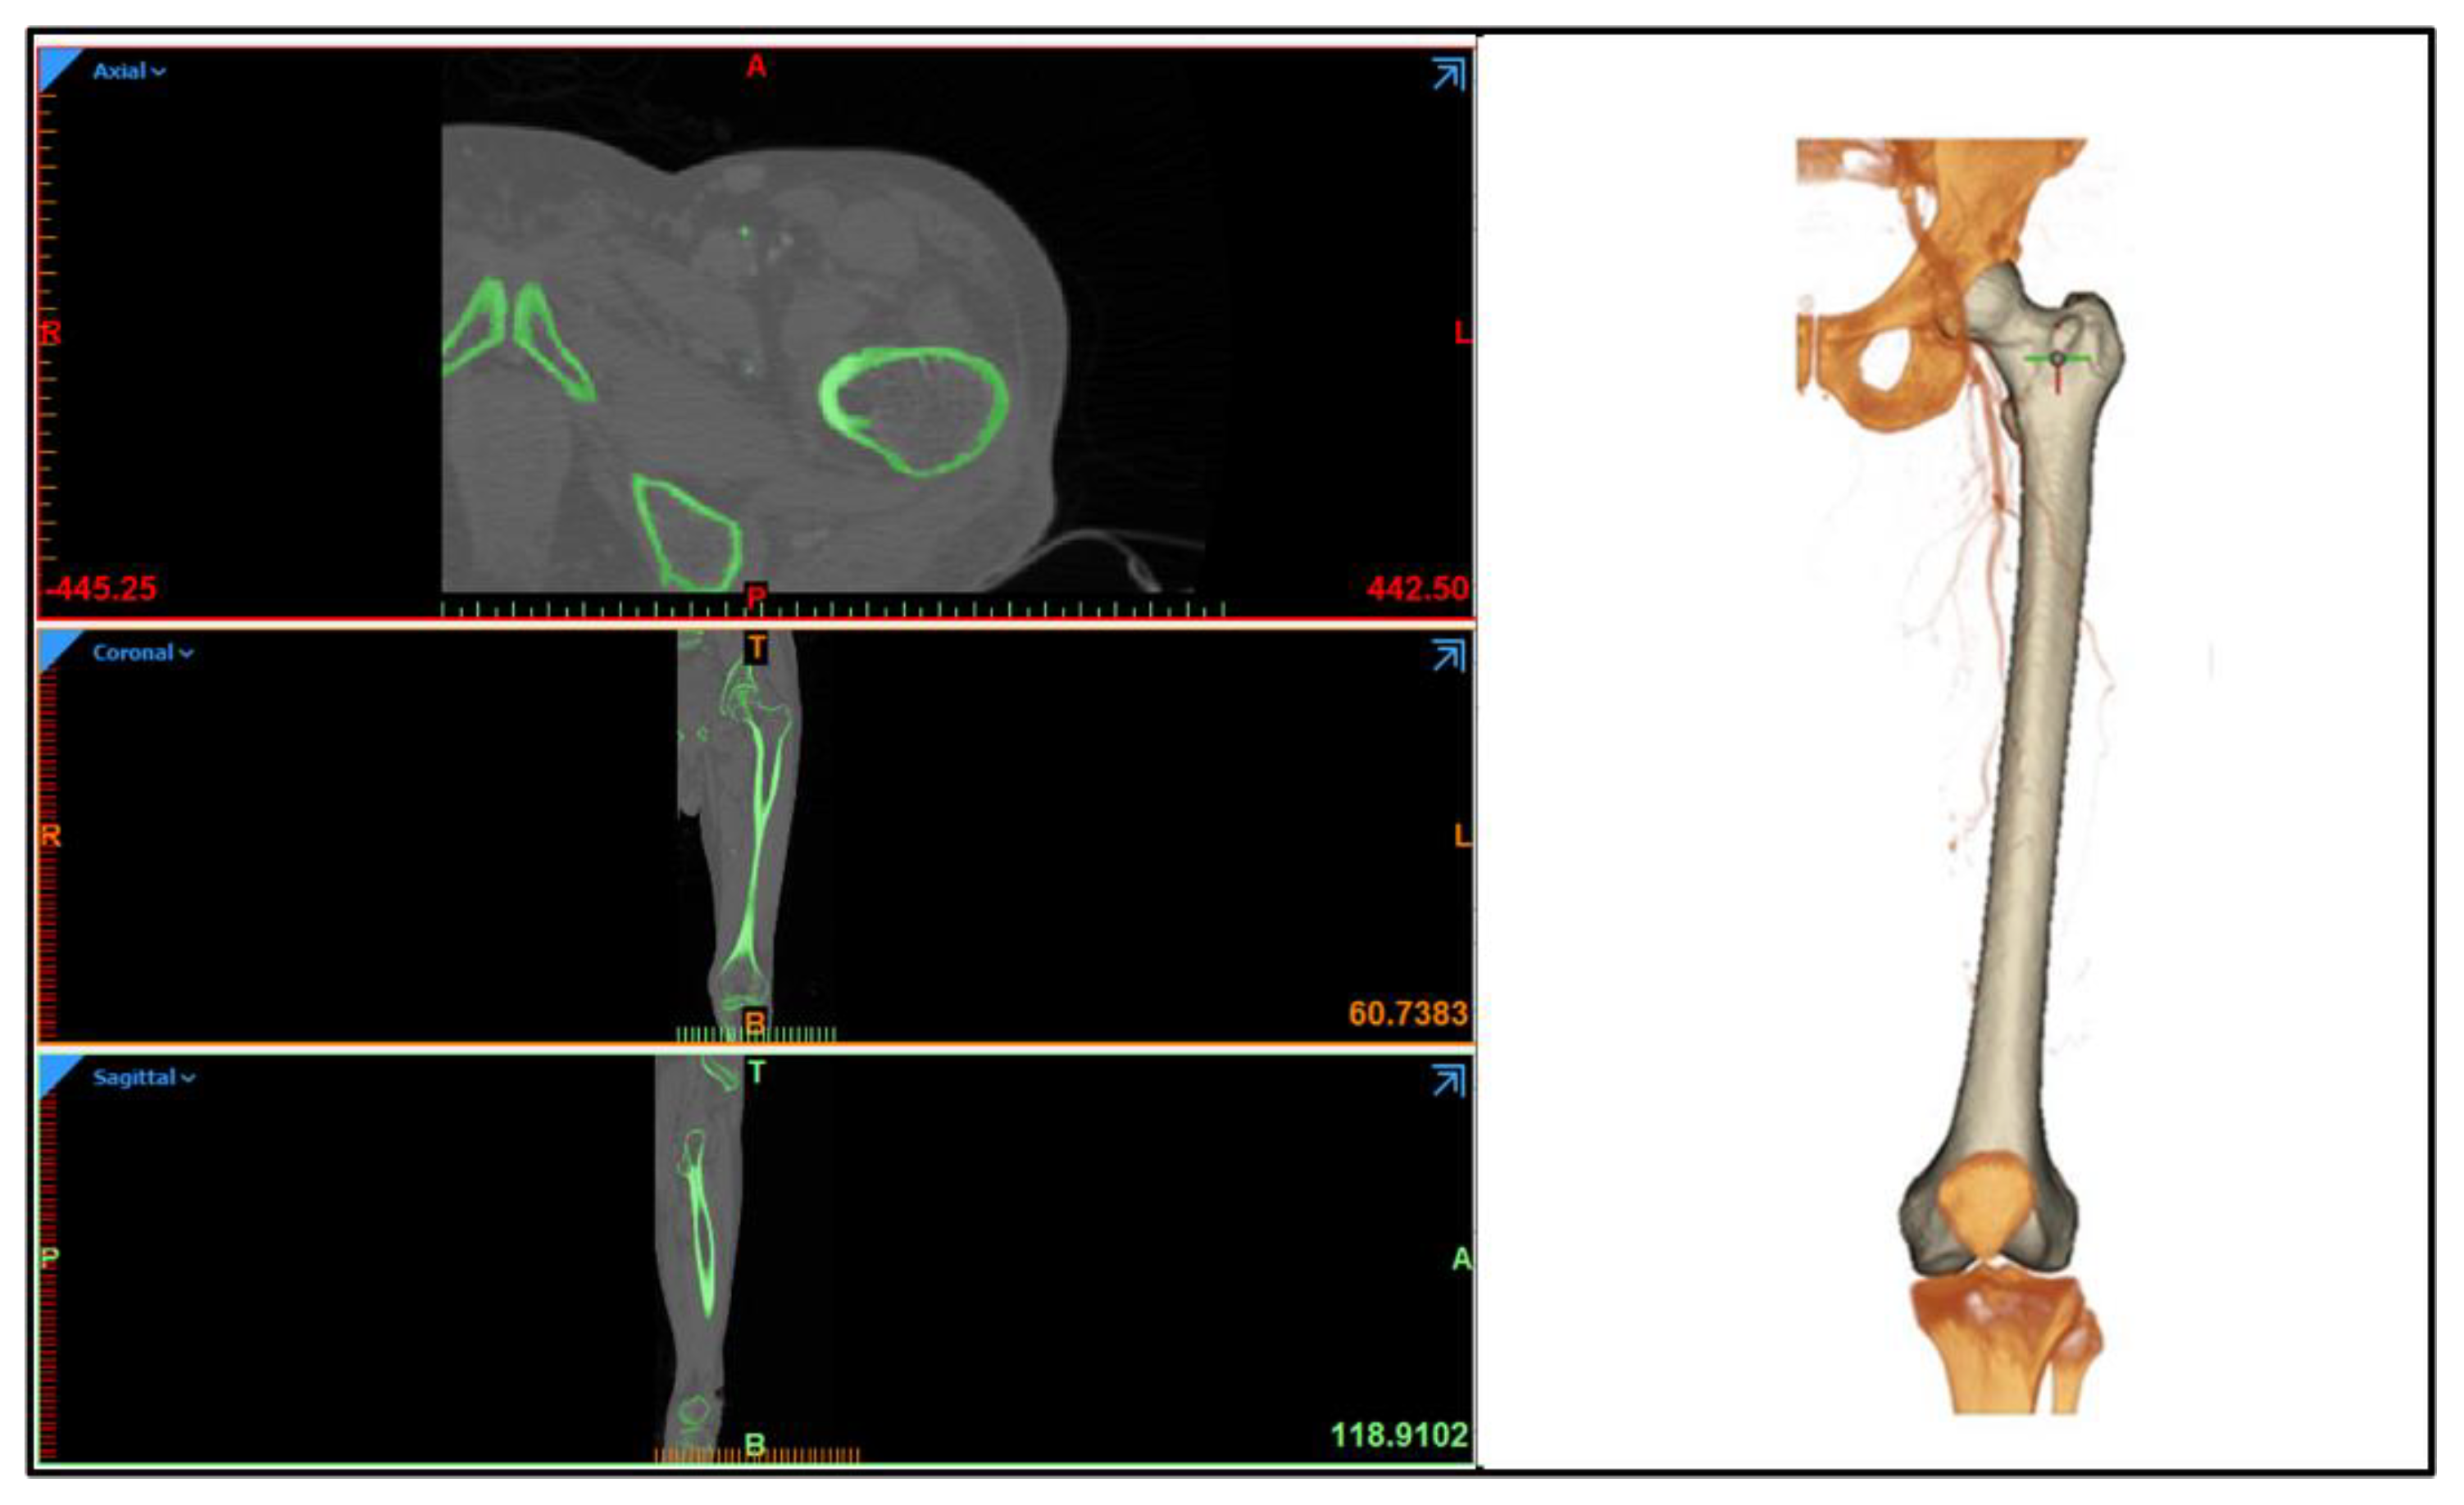

Therefore, the constructed unit cell was used to develop patient-specific implants for critical-size femur defects of 50 mm and studied to determine their behavior in the biomechanical environment. A standard CT scan procedure was followed to obtain cross-sectional images of femur anatomical locations from the subject to generate a femur solid model, after written informed consent, followed by guidelines approved by the Ethical Committee of the Institute of Medical Sciences, Banaras Hindu University, on the use of computed tomography (CT) images. To develop a three-dimensional (3D) reconstruction of the femur bone, Materialise MIMICS 18.0 (Materialise, Leuven, Belgium) software was utilized. A semi-automatic algorithm, known as region-grow, was applied with a Hounsfield threshold range of 230 to 1883 HU, that adequately captured the cortical and cancellous range to extract the bony part of the femur. Figure A2 (left) depicts cross-sectional views of the femur in various orientations, whereas Figure A2 (right) depicts the 3D model. The model was exported in STL format to the FreeCAD software package and a similar procedure discussed in Section 2.2 was employed to convert femur STL to Solid Initial Graphics Exchange Specification (IGES) format.

Figure A2. (Left): The cross−sectional images of the femur in axial, coronal, and sagittal views show the threshold of the bony area. (Right): Generated 3D solid model of femur used in the study.